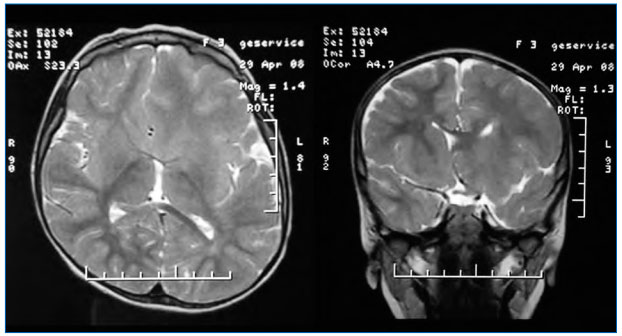

Следует заметить, что топирамат хорошо зарекомендовал себя как антиэпилептический препарат выбора при церебральных дисгенезиях, включая фокальные кортикальные дисплазии, а также диффузных аномалиях развития, изолированных и в структуре нейрокожных синдромов. Позитивный эффект применения топирамата при туберозном склерозе был отмечен в исследовании Дорофеевой М.Ю. и соавт. (2005) [9]. Топирамат играет важную роль для сдерживания приступов у пациентов, являющихся кандидатами на хирургическое вмешательство, так как таким пациентам не рекомендуется терапия вальпроатами с целью снизить вероятность повышенной кровоточивости во время операции. В нашем исследовании у девочки с гемимегалэнцефалией (рис. 3а и 3б) была достигнута клиническая ремиссия на фоне комбинации топамакса и кеппры.

Рисунок 3а

МРТ больной Д.У., 3 года. Гемимегалэнцефалия левой гемисферы, выраженной преимущественно по лобарному (переднему квадрантному) типу с максимумом диспластических изменений в левой лобной доле.